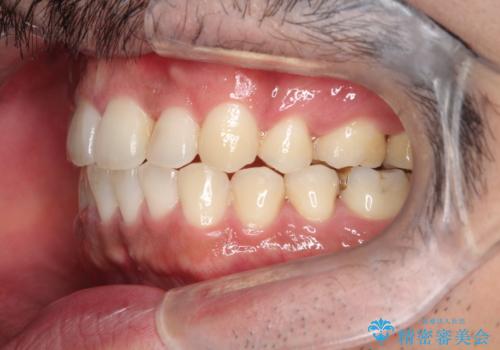

出っ歯の抜歯矯正 裏側ワイヤーによる目立たない矯正

- 出っ歯が気になるとのことで来院されました。

上顎の前から4番目の歯を両側、合計2本抜歯して矯正する計画としました。

目立たない装置がご希望でしたので、上下裏側ワイヤー装置を選択されました。